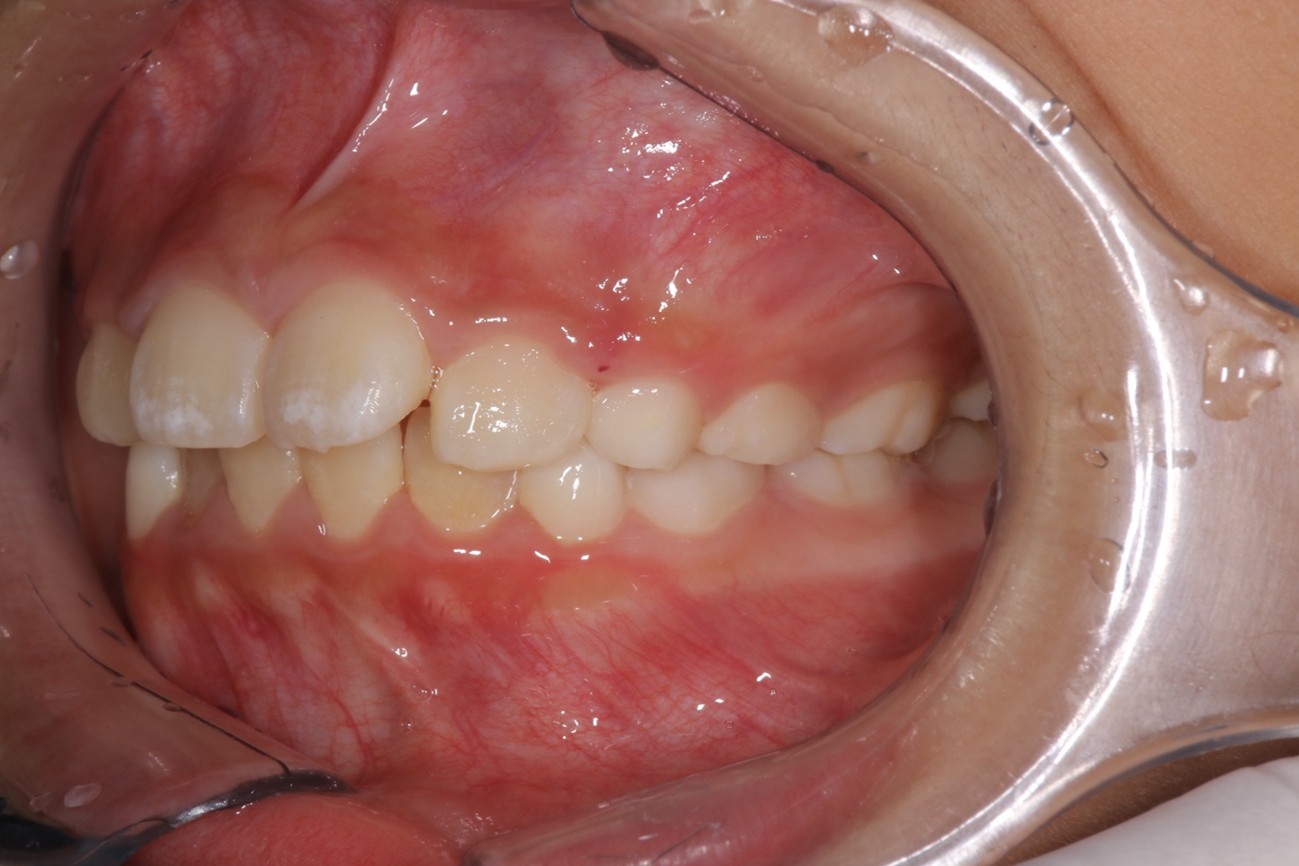

小児矯正

小児矯正 プレオルソ